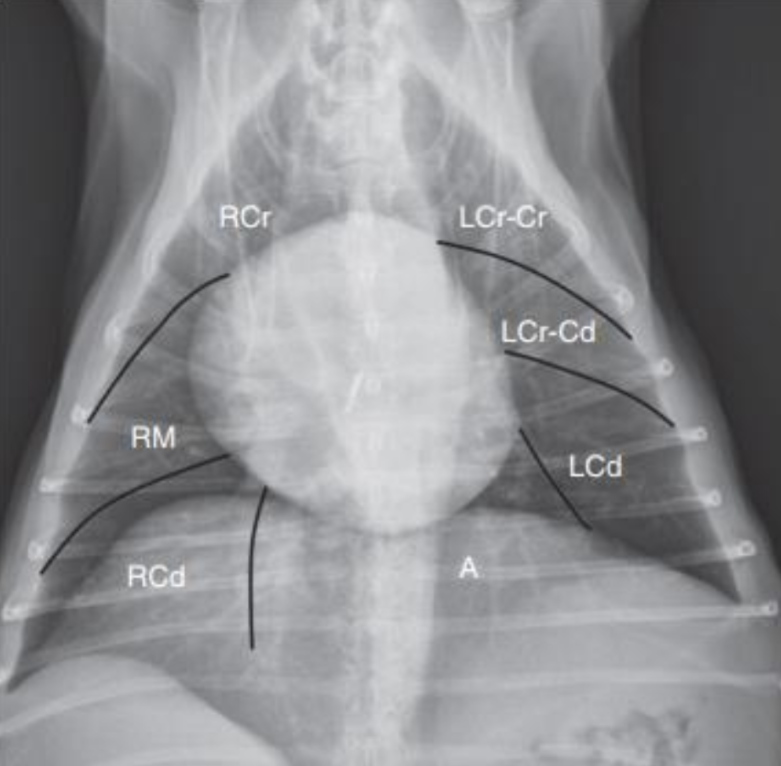

1. Normal Anatomy

| 정상적인 공기의 흐름 : Trachea - Bronchus - Bronchioles - Lung |

| Upper respiratory system |